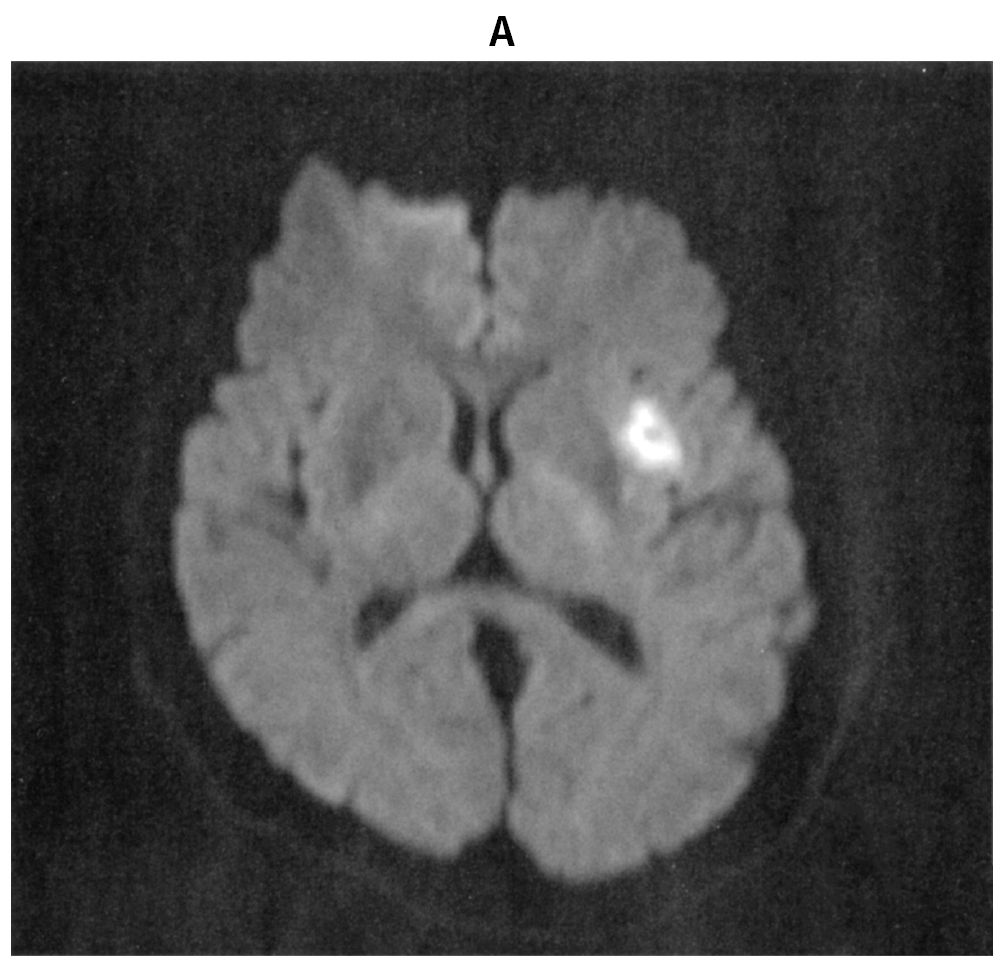

70歳の男性。65歳時に発作性心房細動を指摘されていた。農作業中に吐血し,胃潰瘍穿孔のため,入院した。開腹手術を受け,経過良好のため,退院を予定していた。手術から5日後の午後1時に突然,言葉がしゃべれなくなった。その後,右半身の脱力が出現したため,午後1時25分に病棟看護師から研修医へ連絡があった。意識レベルはJCSⅠ-2。身長171cm,体重65kg。体温36.2℃。脈拍76/分,不整。血圧170/102mmHg。左共同偏視,運動失語,右片麻痺を認めている。NIHSS〈NIH stroke scale〉は16/42点であった。血液所見:赤血球368万,Hb 9.2g/dL,Ht 35%,白血球11,600,血小板16万。12誘導心電図で心房細動を認める。午後2時の頭部単純MRIの拡散強調像(A)と頭部MRA(B)とを下に示す。